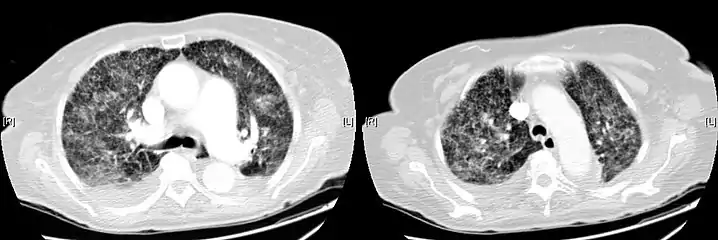

Miliary tuberculosis is a form of tuberculosis that is characterized by a wide dissemination into the human body and by the tiny size of the lesions (1–5 mm). Its name comes from a distinctive pattern seen on a chest radiograph of many tiny spots distributed throughout the lung fields with the appearance similar to millet seeds—thus the term "miliary" tuberculosis. Miliary TB may infect any number of organs, including the lungs, liver, and spleen.[2] Miliary tuberculosis is present in about 2% of all reported cases of tuberculosis and accounts for up to 20% of all extra-pulmonary tuberculosis cases.[3]

Testing for miliary tuberculosis is conducted in a similar manner as for other forms of tuberculosis, although a number of tests must be conducted on a patient to confirm diagnosis.[4] Tests include chest x-ray, sputum culture, bronchoscopy, open lung biopsy, head CT/MRI, blood cultures, fundoscopy, and electrocardiography.[10] The tuberculosis (TB) blood test, also called an Interferon Gamma Release Assay or IGRA, is a way to diagnose latent TB. A variety of neurological complications have been noted in miliary tuberculosis patients—tuberculous meningitis and cerebral tuberculomas being the most frequent. However, a majority of patients improve following antituberculous treatment. Rarely lymphangitic spread of lung cancer could mimic miliary pattern of tuberculosis on regular chest X-ray. [15]